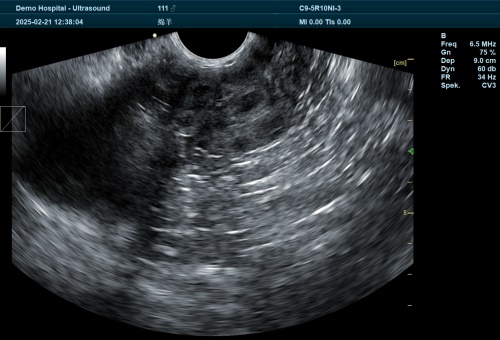

Veterinarians tend to stress operator skill and probe selection. A good-quality convex probe with a frequency around 5 MHz works best for adult ewes. Others use higher-frequency linear probes for ewes around 35–45 days when fetuses are small but near the surface.